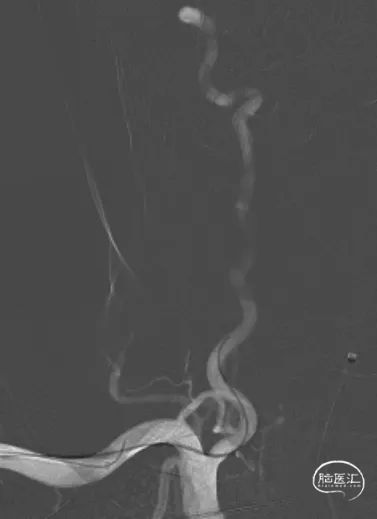

术前影像学资料

右侧椎动脉

左侧椎动脉